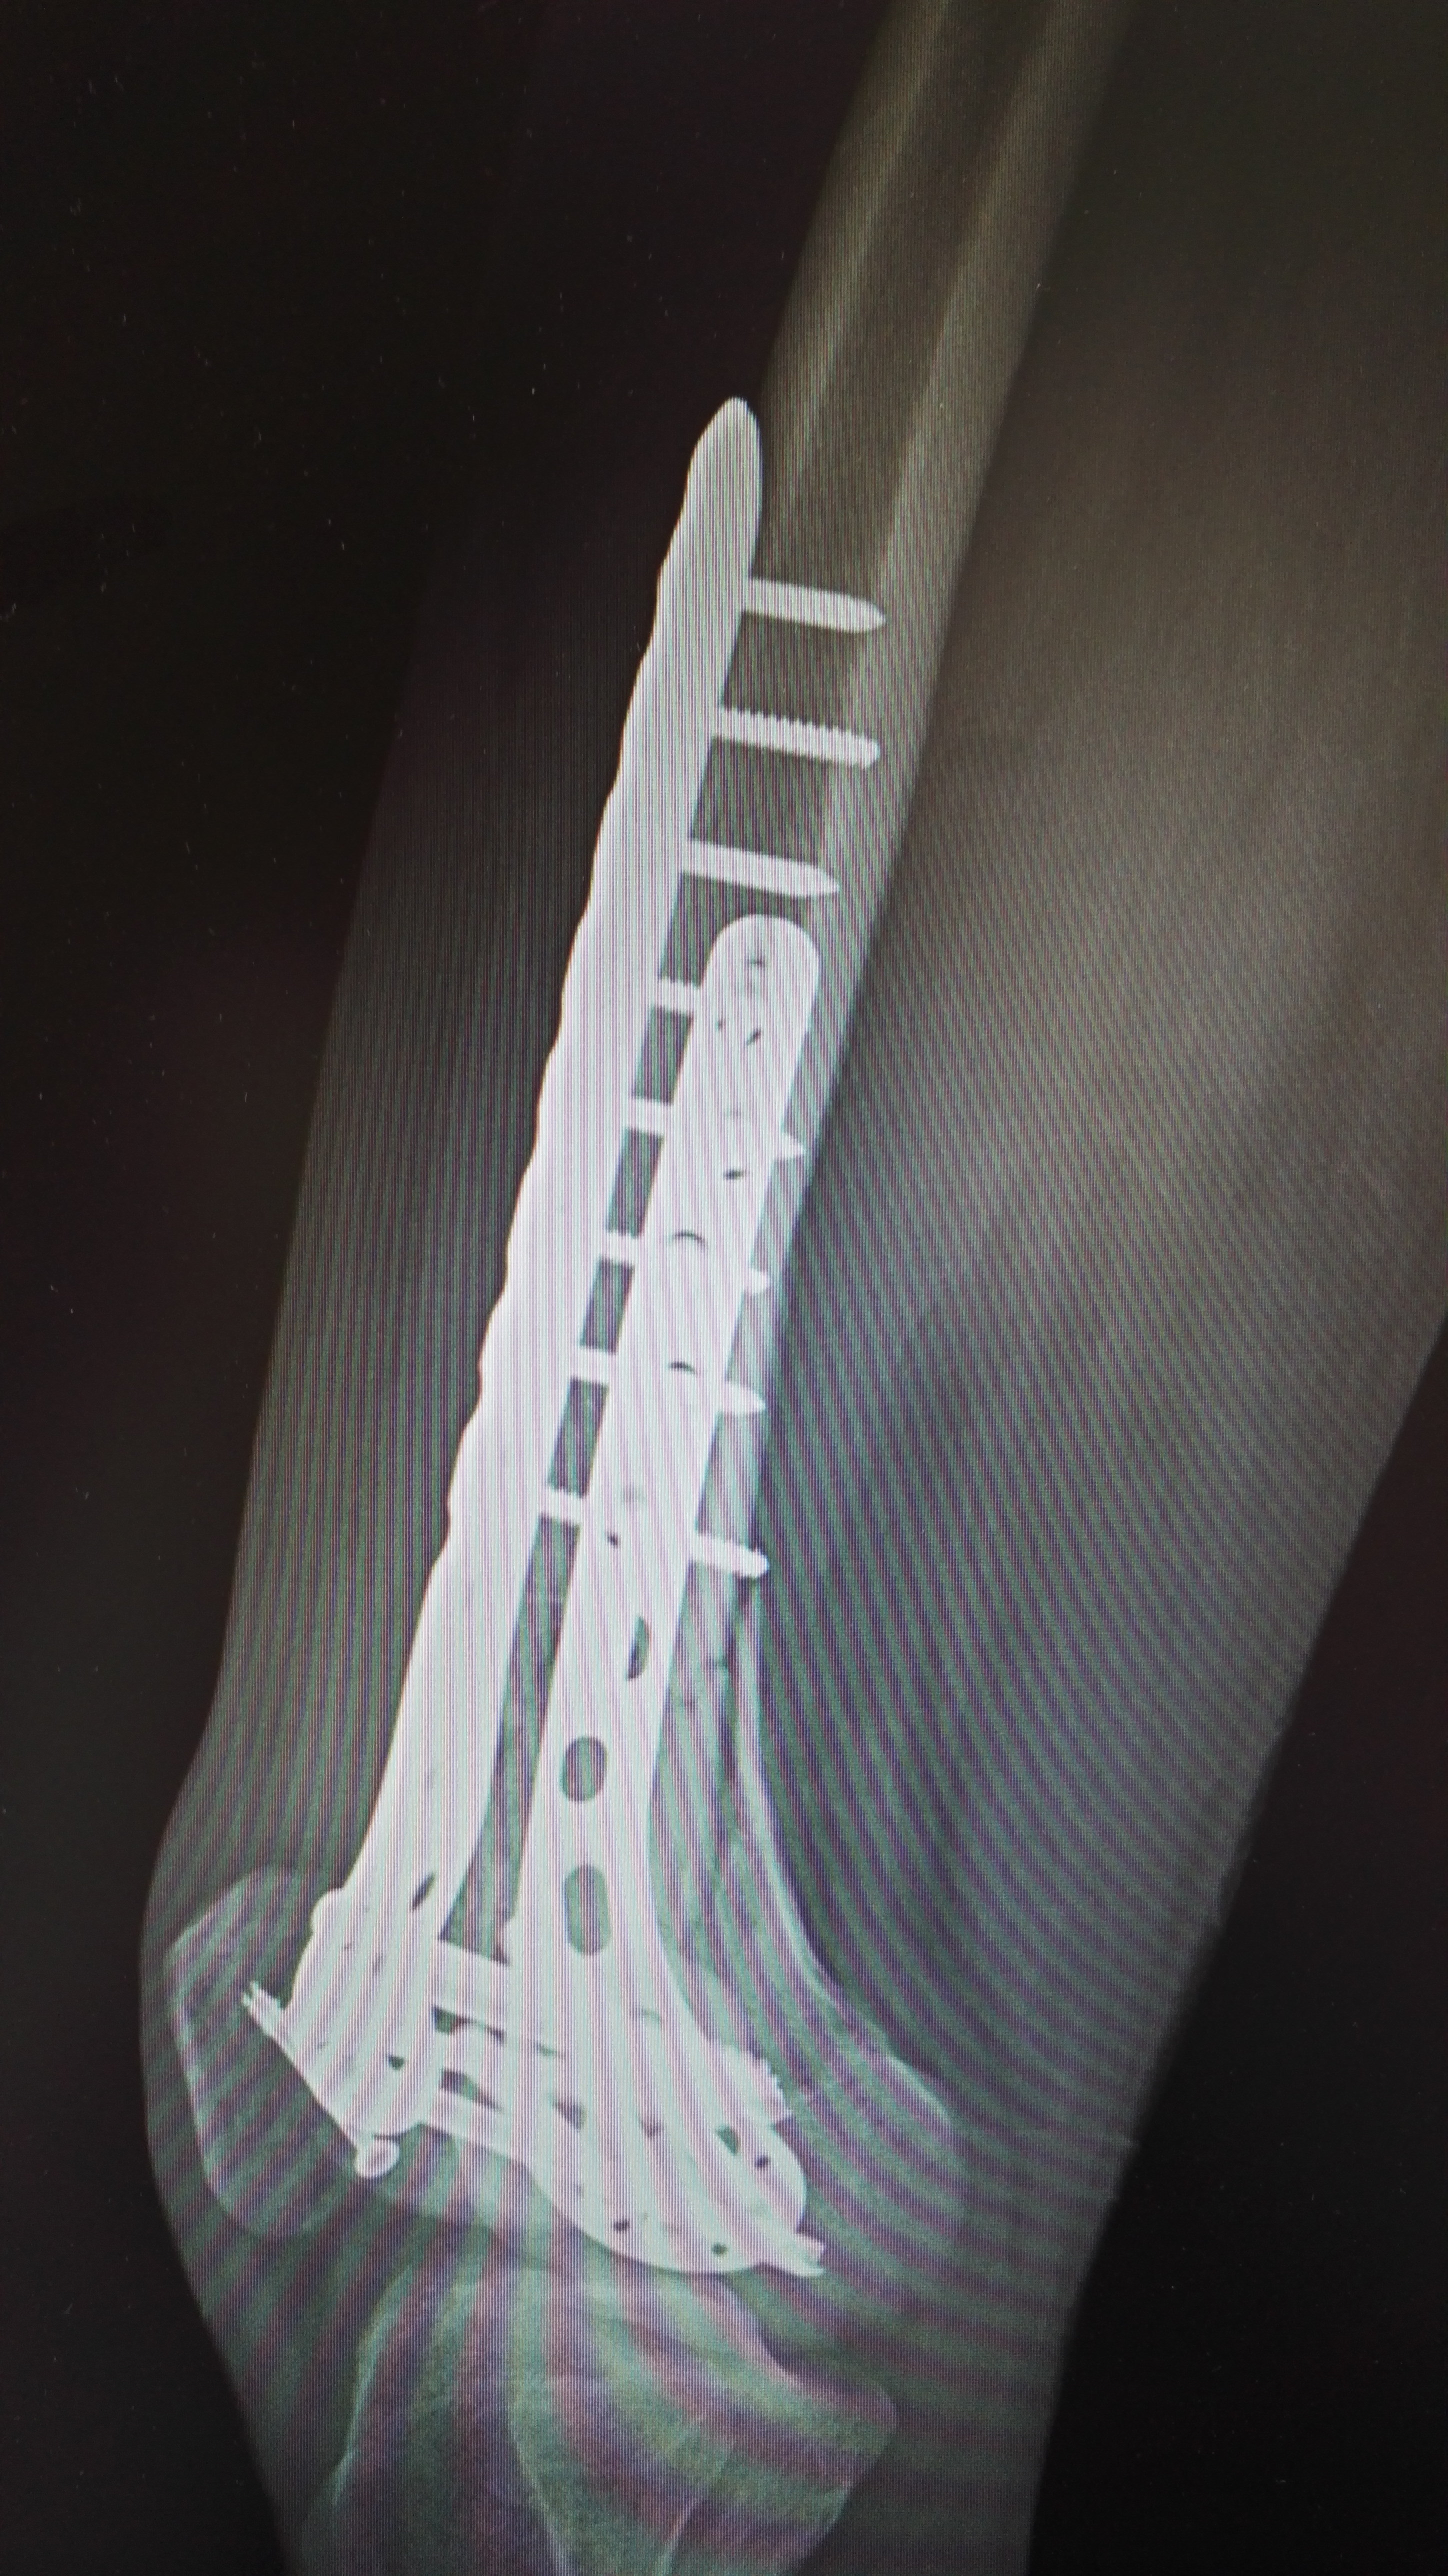

下肢股骨远端骨折1例,伴髌骨骨折 - 好大夫在线

图片尺寸2896x5152